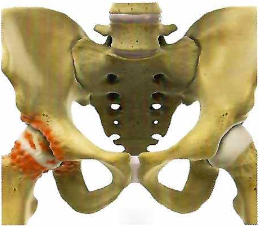

Асептический некроз головки бедренной кости.

Асептический некроз кости (остеонекроз) - это тяжелое заболевание, связанное с гибелью костных клеток в определенном участке костной ткани, с нарушением кровоснабжения, быстро приводящее к развитию вторичного артроза/артрита прилежа щего сустава. Наиболее частой локализацией является головка кости, на втором месте по распространению находятся мыщелки бедренной и большеберцовой костей, реже головка плечевой кости, таранная кость. В поздних стадиях и при выраженных болевых симптомах, показано оперативное лечение! Лечение по ОМС в частной клинике. #dr.bondorenko

Асептический некроз кости (остеонекроз) - это тяжелое заболевание, связанное с гибелью костных клеток в определенном участке костной ткани, с нарушением кровоснабжения, быстро приводящее к развитию вторичного артроза/артрита прилежа щего сустава. Наиболее частой локализацией является головка кости, на втором месте по распространению находятся мыщелки бедренной и большеберцовой костей, реже головка плечевой кости, таранная кость.

В поздних стадиях и при выраженных болевых симптомах, показано оперативное лечение!